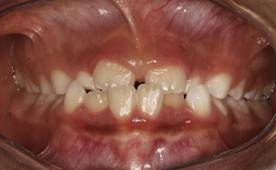

Análisis intraoral: Al observar la boca del paciente nos encontramos que la mucosa está húmeda y lubricada con pigmentación melánica, el frenillo es de inserción mucosa; hay poca inflamación de las encías. El paladar duro es profundo. El paciente está en dentición mixta, existe una mordida cruzada anterior con apiñamiento en el sector anteroinferior. En el arco superior se observa un diastema entre los incisivos centrales superiores permanentes, también se observa que estos dientes están ligeramente rotados. La relación molar de ambos lados es de clase III y la relación de los caninos deciduos también es de clase III.

Fig.3 Fotografía intraoral de frente Fig.

4 Fotografía intraoral de 45°

Fig. 5 Fotografía intraoral lado derecho Fig. 6 Fotografía intraoral lado izquierdo

Análisis de los modelos: El arco superior tiene forma de U. El arco inferior tiene más una forma rectangular y en la vista oclusal, se confirma el apiñamiento de los incisivos inferiores permanentes. La discrepancia en el arco superior nos dio de -1.2 mm y en el arco inferior fue de -2mm.

Fig. 7 Modelo superior en una vista oclusal Fig. 8 Modelo inferior es una vista oclusal